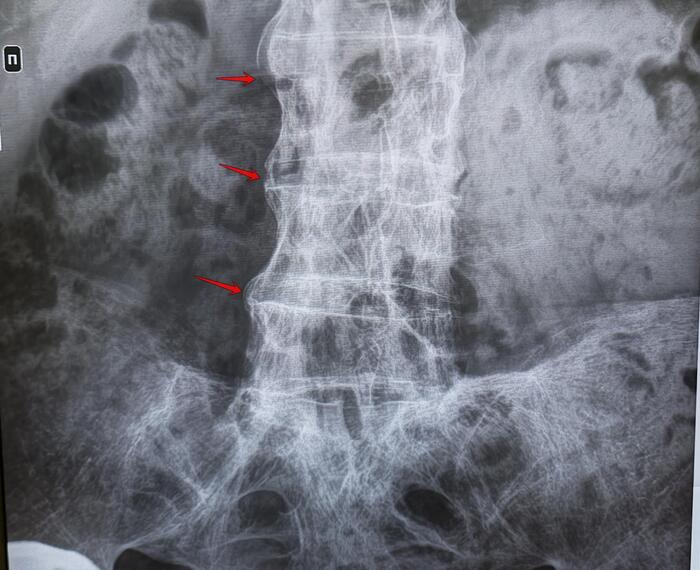

Рентгенография - в начальной стадии при подагре почти не дает информации; при длительном течении, когда кристаллы накапливаются внутри кости, их видно как четкие округлые образования - “пробойник ”.

При пирофосфатной артропатии иногда можно увидеть кальцификацию суставного хряща.

- Рентгенография - в основном для исключение перелома (если была травма), определения стадии деструкции сустава.